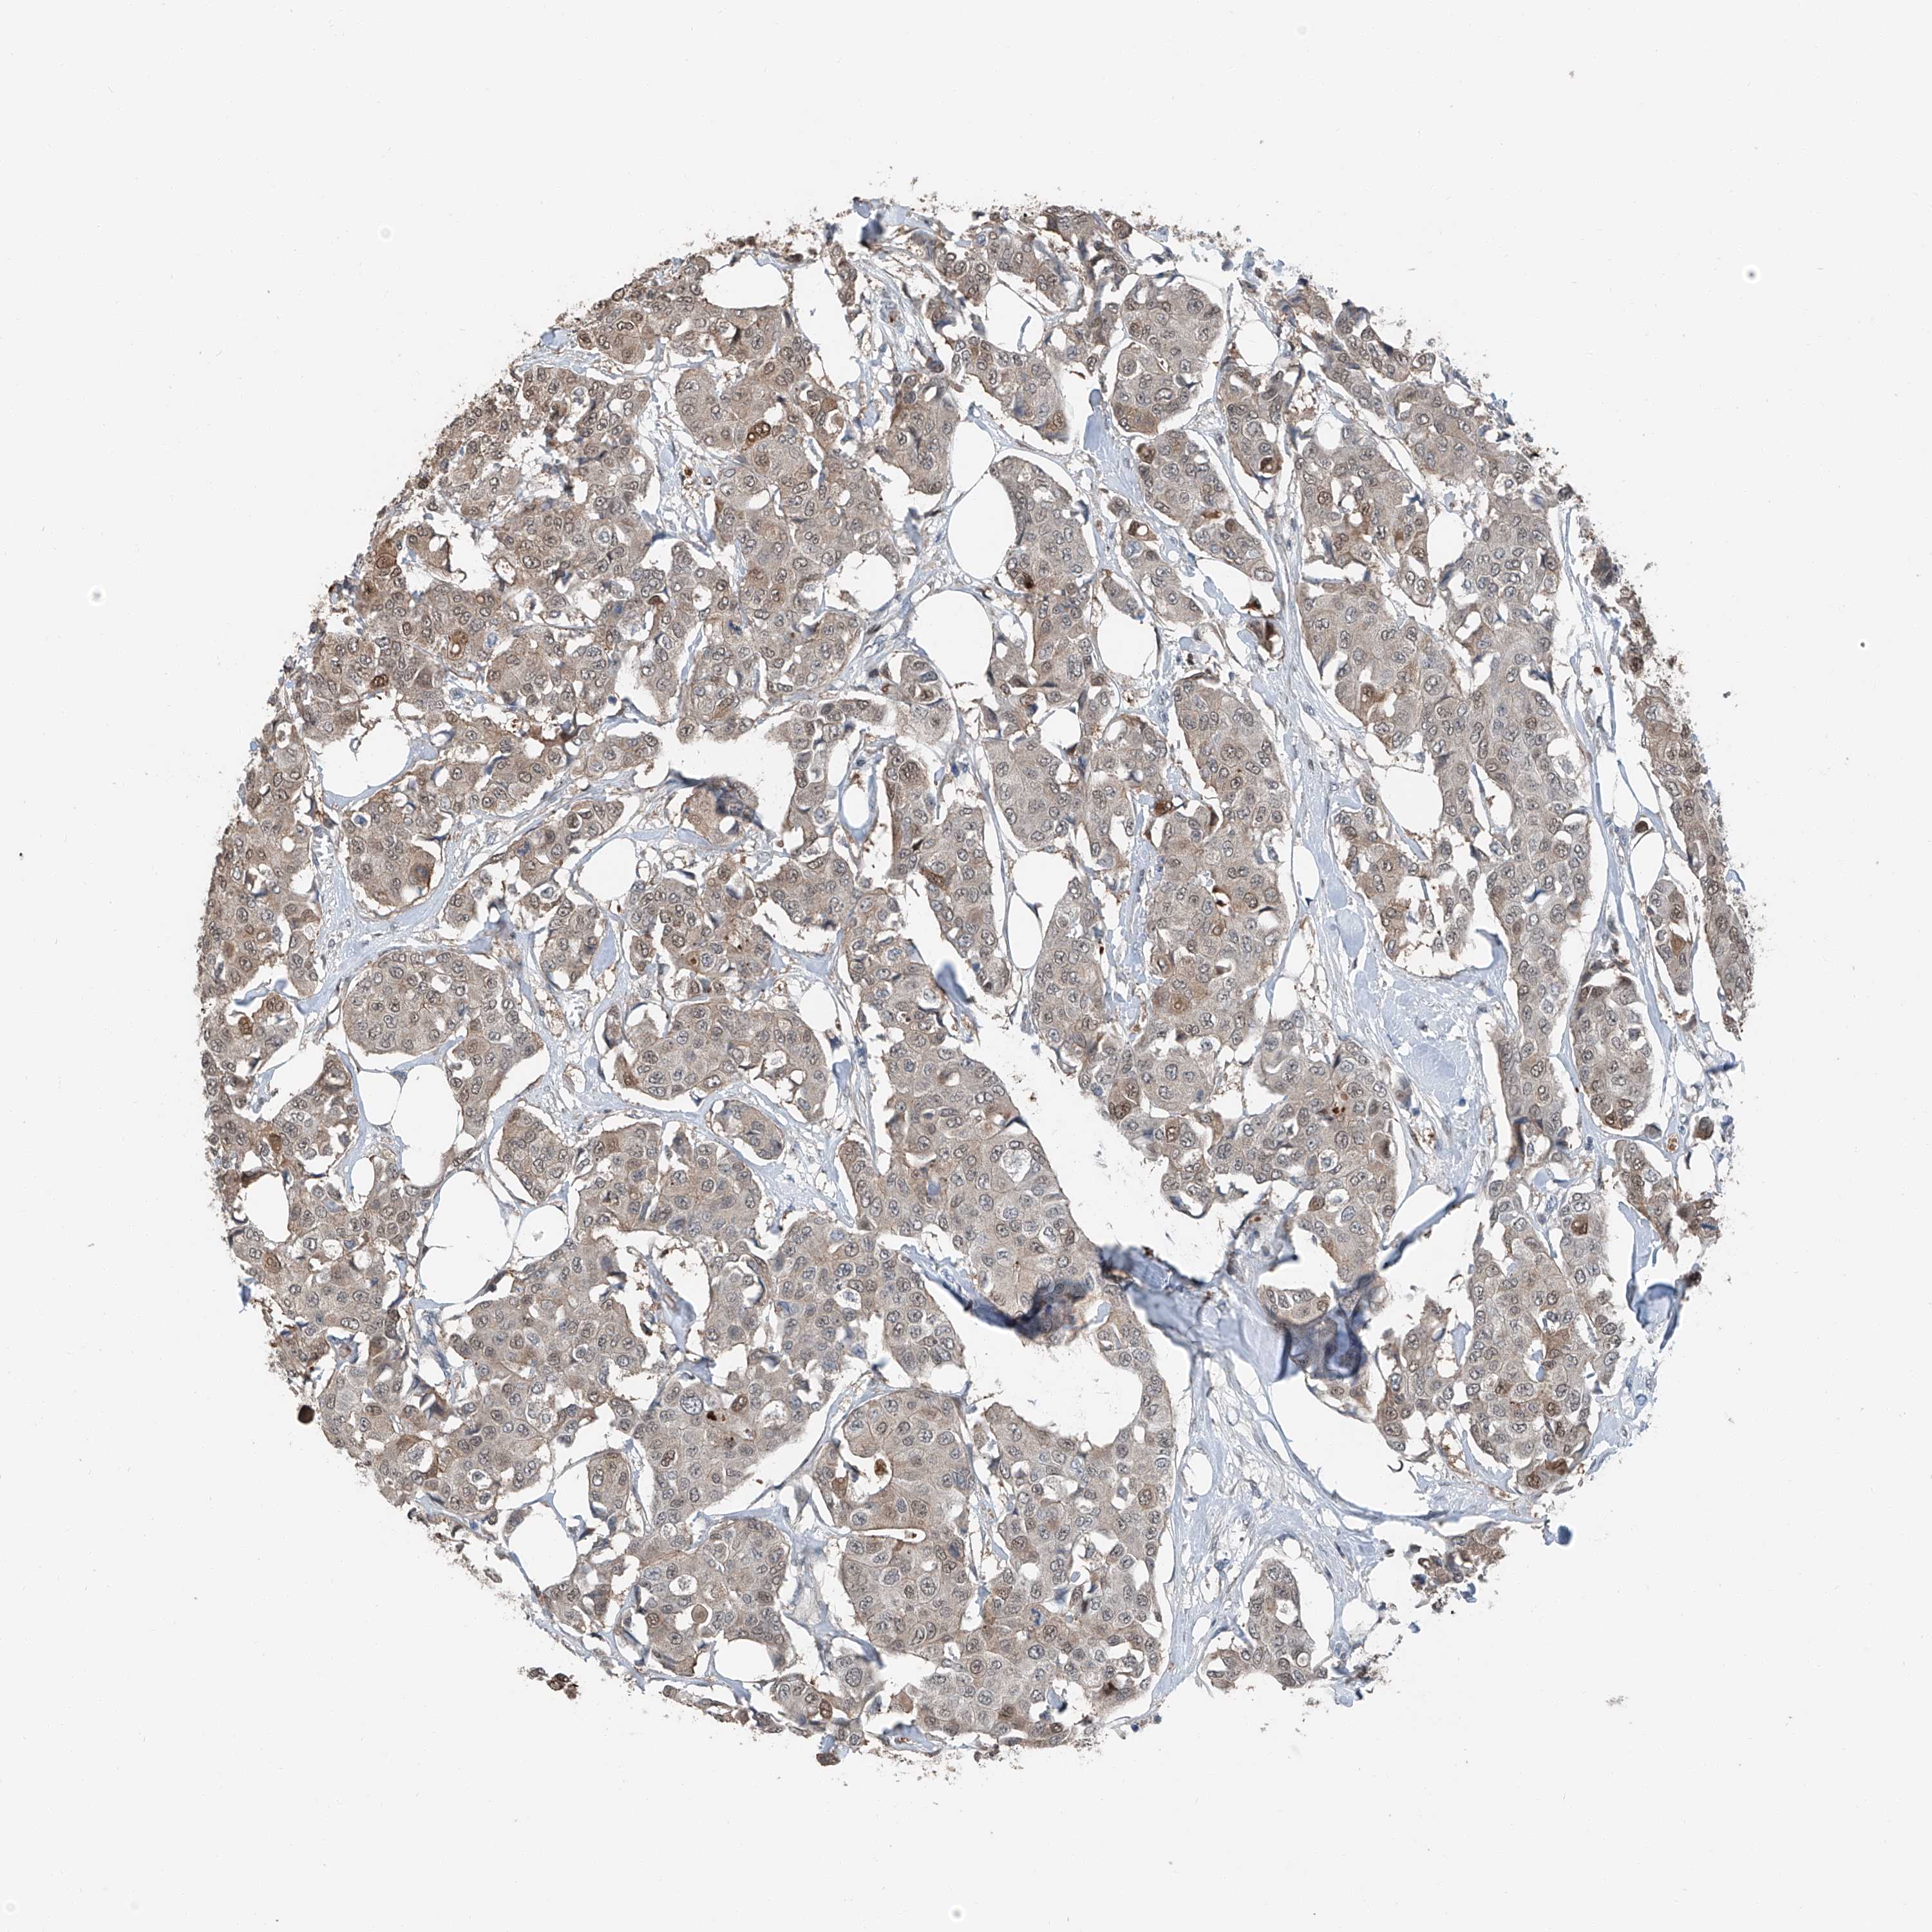

CANCER BREAST CANCER Show tissue menu

BRCA TCGA BRCA VALIDATION PROTEIN EXPRESSION